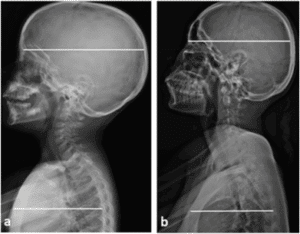

Diving into the literature of pediatric chiropractic can be confusing. What many studies, randomized control trials, and systematic reviews concluded is that chiropractic care for pediatrics is safe and effective for treating musculoskeletal conditions and spinal posture correction. This evidence is based on x-ray (specifically using the Chiropractic Biophysics techniques), and improvement of symptoms. These symptoms are often movement deficits, such as only breast feeding on one side, inability to meet developmental milestones, and unexplained crying. Other signs of physical pain are included as well. The NIH, The Journal of Churna Manual Medicine for Spine and Nerves, Chiropractic News, Journal of Contemporary Chiropractic, and Journal of Integrative and Complementary Medicine have all published research in the past 5 years that support the safety and use of chiropractic care for musculoskeletal conditions.